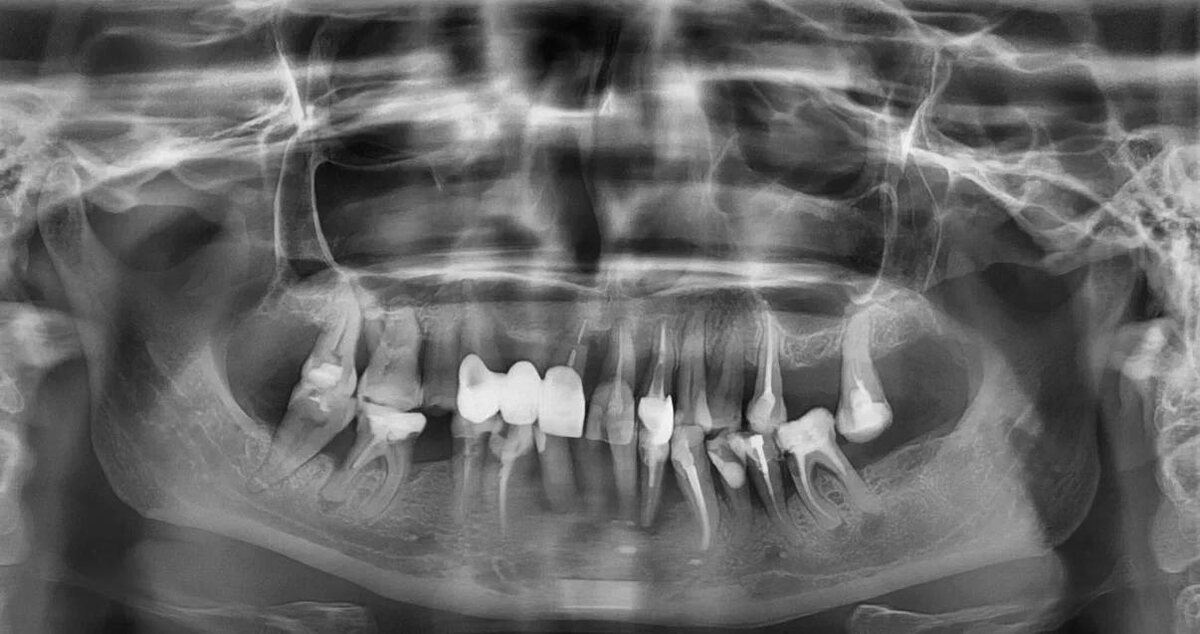

Этот случай — идеальный пример. Пациентка, Ольга Ивановна, пришла с жалобами на периодическую боль и дискомфорт. Внешне — ряд зубов, некоторые даже под старыми коронками. Но один снимок — компьютерная томограмма (КТ) — рассказал совершенно другую, шокирующую историю. Это был приговор для большей части зубов.

Что скрывалось за «нормальной» улыбкой? На снимке мы увидели картину тотального разрушения:

🔻 Массивная убыль кости. Костная ткань, которая должна плотно обхватывать корни, была почти полностью разрушена. Зубам просто не на чем было держаться.

Бомбы замедленного действия — хронические воспаления у корней (гранулёмы и кисты). Это тихие очаги инфекции, которые отравляют организм каждый день.

Корни, которые уже не корни. Они были разрушены, несостоятельны и служили лишь рассадником бактерий.

Старые конструкции, висящие в воздухе. Пломбы и коронки, которые давно лишились надежной опоры и создавали угрозу для соседних зубов.

Подвижность. Зубы, которые уже не могли выполнять свою главную функцию — жевать.

Вывод был однозначным: эти зубы не просто были больны. Они были источником постоянной инфекции и боли, «тянули» за собой здоровье всего организма и не подлежали восстановлению. Попытка сохранить их была бы не только бесполезна, но и опасна.